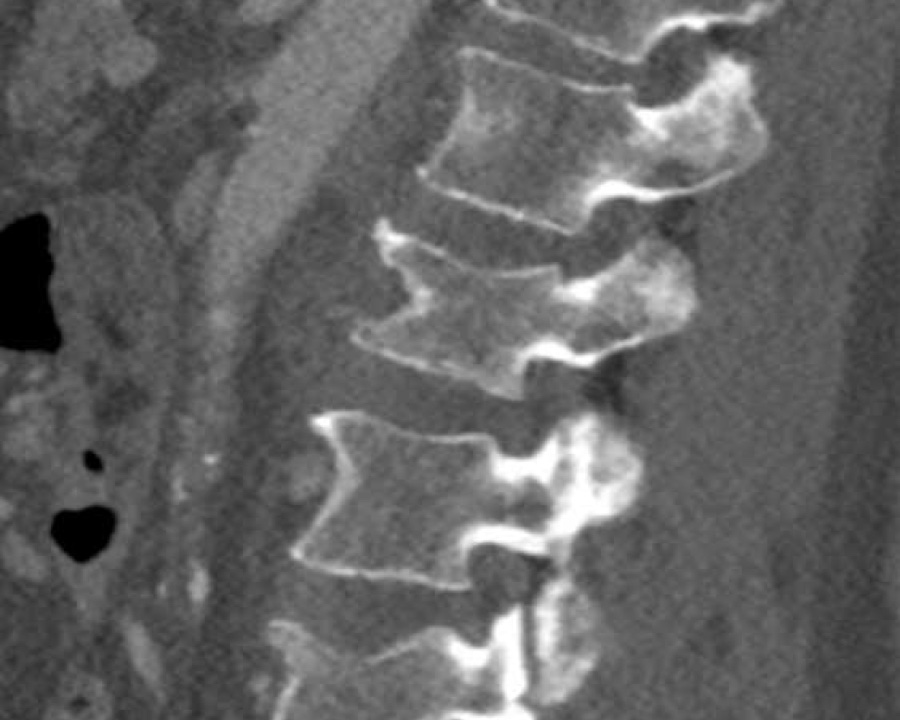

A2 Split fracture

A2 is a fracture of both endplates without involvement of the posterior wall of the vertebral body.

What is the highest AO-type of injury?

Findings:

- No C or B injury

- Fracture of the vertebral body with involvement of both endplates (1+1 points), no posterior wall involvement

Conclusion

injury type A2